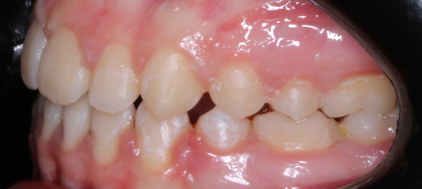

Llama la atención a primera vista la mordida abierta bilateral, especialmente pronunciada entre el cuadrante 1 y 4 debido a una interposición lingual en posición estática. Entre otros hallazgos fundamentales, observamos: un patrón dolicofacial severo (VERT: -2), una compresión de la arcada superior que cursa con un perfil y relación oclusal de clase III y la rotación del 35 y 45. Este caso se trató con un disyuntor, exodoncias de 44 y 34, brackets convencionales y educadores para rehabilitación de la lengua en un tiempo de 22 meses. Aunque estoy satisfecho con el resultado final, me hubiera gustado clavar la interscuspidación de premolares en el cuadrante I y IV, y mejorar la relación oclusal de cuadrante II y III. Sin embargo, lo bonito, es que hay a veces, en la ortodoncia real, que el paciente está satisfecho y quiere terminar antes de tiempo, o por el contrario, que el profesional intenta pero no consigue el resultado deseado. Y a mí más que compartir casos perfectos, me gusta mostrar mis errores, mi realidad.

La ilustración nos deja entrever algo tan fácil como que en un paladar pequeño no entra una lengua grande. Y viceversa, en un paladar grande entra una lengua grande. Llevándonos dicha explicación al caso que nos atañe, podemos ver  en la fotografía lateral del lado derecho como la lengua escapa y busca espacio, de manera permanente, entre el cuadrante 1 y 4,  estímulo que mantenido en el tiempo generó en una mordida abierta lateral.